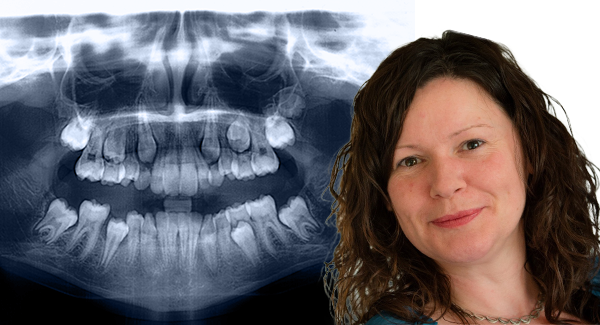

Janice St. John-Matthews